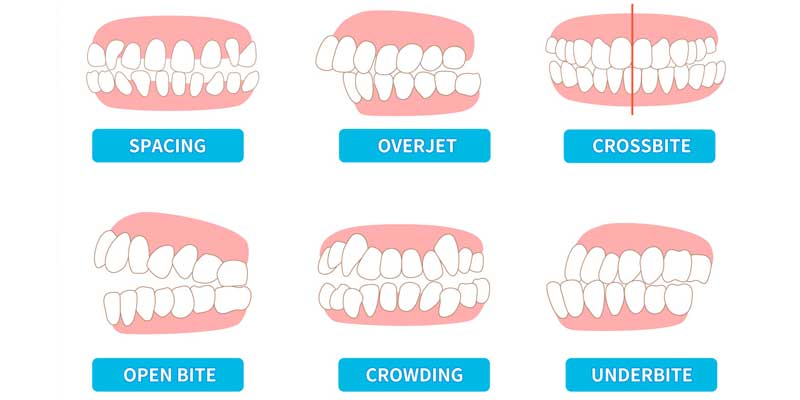

مال اکلوژن اصطلاحی دندانی است که به هرگونه انحراف از اکلوژن ایده آل اشاره دارد؛ به عبارت دیگر، زمانی که دندان های فک بالا و پایین به درستی روی هم قرار نگیرند یا ارتباط صحیحی نداشته باشند، فرد دچار مال اکلوژن است. این ناهنجاری می تواند به شکل جلو آمدگی فک، عقب رفتگی، کج بودن دندان ها، یا شلوغی بیش از حد دندان ها ظاهر شود.

در حالت اکلوژن نرمال، دندان های فک بالا کمی جلوتر از دندان های فک پایین قرار می گیرند و دندان های آسیای بالا و پایین به درستی در هم قفل می شوند. اما در حالت مال اکلوژن، این هماهنگی وجود ندارد و ممکن است مشکلاتی مانند کراس بایت، اپن بایت، اوربایت یا آندربایت دیده شود. این تفاوت در اکلوژن، به مرور زمان می تواند منجر به مشکلات عملکردی، زیبایی و حتی آسیب به مفصل فک شود.

مال اکلوژن بر اساس نحوه قرارگیری فک ها و دندان ها در کلاس های مختلفی طبقه بندی می شود:

- کلاس I (اکلوژن نرمال با شلوغی یا چرخش دندان ها)

در این نوع، ارتباط کلی فک ها طبیعی است اما دندان ها ممکن است نامنظم، شلوغ یا چرخیده باشند. - کلاس II (جلو آمدگی فک بالا)

در این حالت، فک بالا جلوتر از فک پایین قرار می گیرد. این نوع مال اکلوژن معمولاً به شکل اورجت یا اوربایت شدید ظاهر می شود. - کلاس III (جلو آمدگی فک پایین)

در کلاس 3، فک پایین از فک بالا جلوتر قرار دارد که می تواند منجر به آندربایت یا “فک جلو آمده” شود. - انحرافات عرضی و عمودی (کراس بایت، اپن بایت، دیپ بایت)

- کراس بایت: دندان های بالا به جای قرارگیری بیرون از دندان های پایین، به داخل آن ها می افتند.

- اپن بایت: هنگام بسته شدن فک ها، برخی دندان های جلویی یا عقبی به هم نمی رسند.

- دیپ بایت: دندان های فک بالا به طور غیرطبیعی دندان های پایین را می پوشانند.